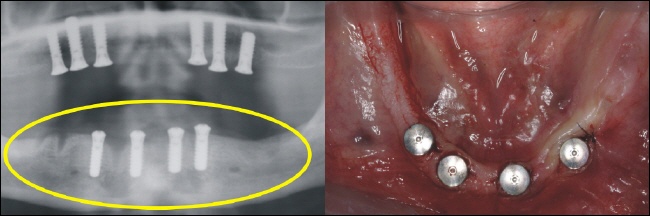

Nach der Einheilzeit werden auf die Implantate Teleskopkronen aufgesetzt, über die der Zahnersatz gesteckt wird (Oberkiefer). |

Nach der Einheilzeit werden auf die Implantate Teleskopkronen aufgesetzt über die der Zahnersatz gesteckt wird (Unterkiefer). |